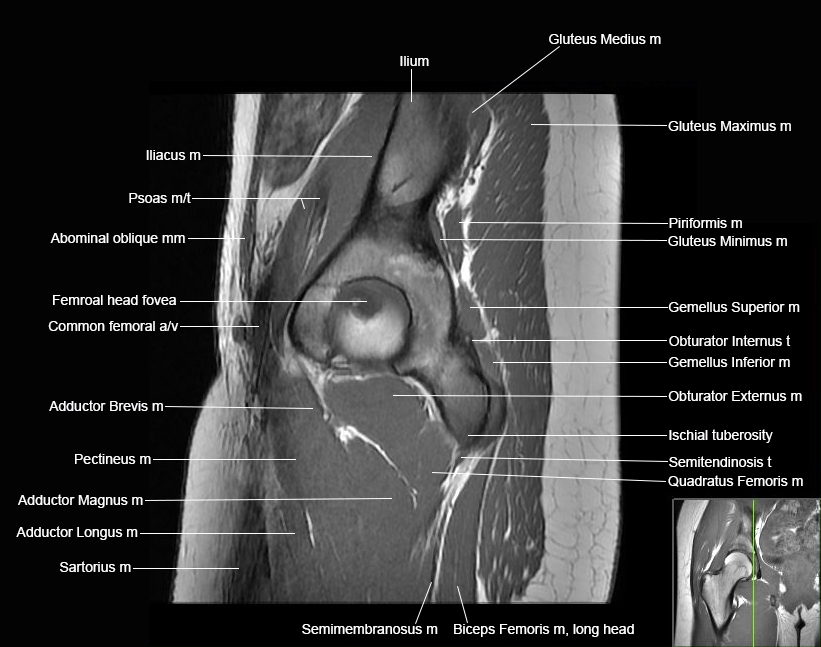

Hip

Basic Hip MRI

MRI Hip Anatomy

Scroll using the mouse wheel or the arrows